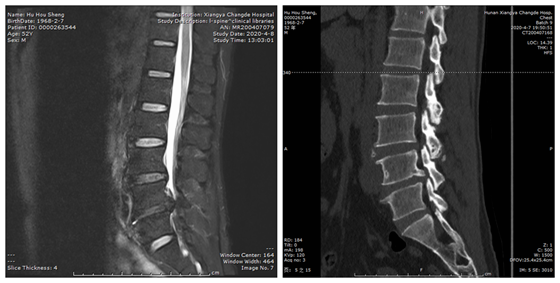

胡先生得知湘雅常德医院骨科在脊柱方面的微创手术创伤小、恢复快,故来到我院就医。陈芳田副主任医师接诊患者后,查看了患者的影像学资料,并对其进行了详细的体格检查,初步考虑为腰椎间盘突出(L4/5),合并椎体后缘增生,该节段椎管严重狭窄导致了患者双下肢麻木、疼痛、间歇性跛行。在完善各项检查后,陈芳田副主任医师告诉患者,他这种情况能进行微创手术,手术切口仅1厘米,而且只需局部麻醉就能完成手术,术后恢复也很快。

患者入院后,在骨科主任张朝跃教授的指导下,经过周密的术前讨论及准备,陈芳田副主任医师团队在局麻下为患者实施了椎间孔镜下腰椎管减压手术(270°减压),术后患者双下肢胀痛即刻消失、麻木明显缓解。

术前

术中

术后